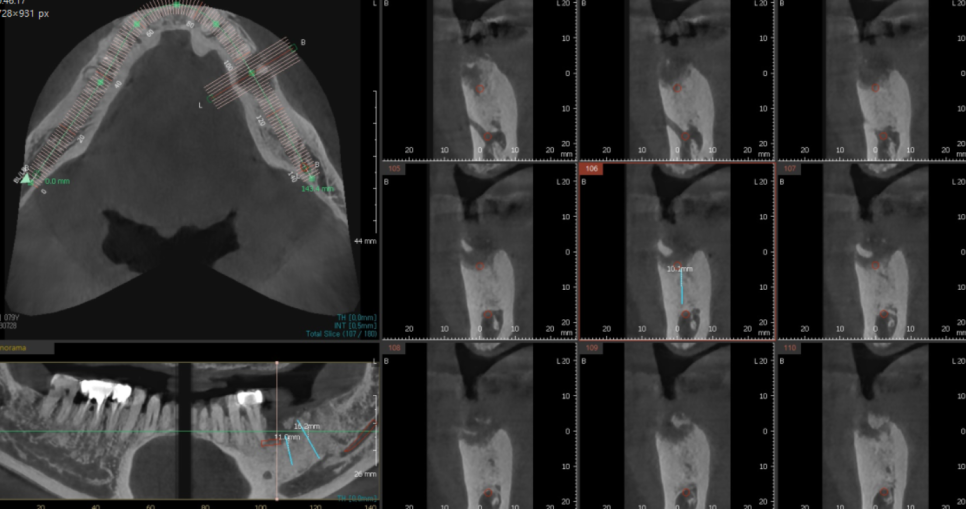

뼈가 다 만들어졌을 때

둔촌동 임플란트 진단을 진행하였습니다.

처음에 분석했을 때와

뼈 이식 후 모습

달라졌기에

2차 분석을 실시

바르디지털 치과인 만큼

내비게이션 임플란트 기술을 사용하여

수술 예측, 분석하였습니다.